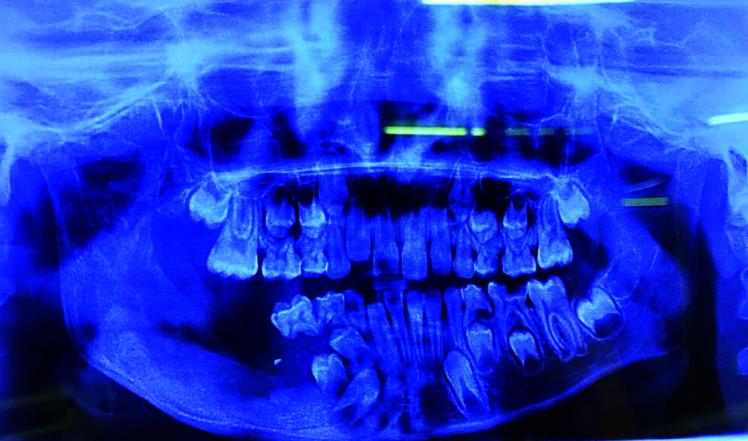

Massive cystic lesions involving a mandible always present a diagnostic and treatment challenge. Unicystic ameloblastoma (UA) is a variant of ameloblastoma encompassing about 6% of ameloblastomas. They represent cystic lesions that reveal clinical and radiographic features of a cyst, but the histopathological features demonstrate a typical ameloblastomatous epithelium lining the cyst. It is a variant of ameloblastoma, usually having clinical and radiographic similarities with dentigerous cysts, hence posing preoperative diagnostic difficulties. Adult treatment protocol cannot be applied to the pediatric population since resection may cause an alteration in craniofacial development leading to functional and esthetical damage, which can directly affect their quality of life. A more conservative approach of enucleating the lesion seems to be a promising treatment modality of UA in the pediatric age group. We present a case of mural variant of UA arising from dentigerous cyst in an 8-year-old male patient.